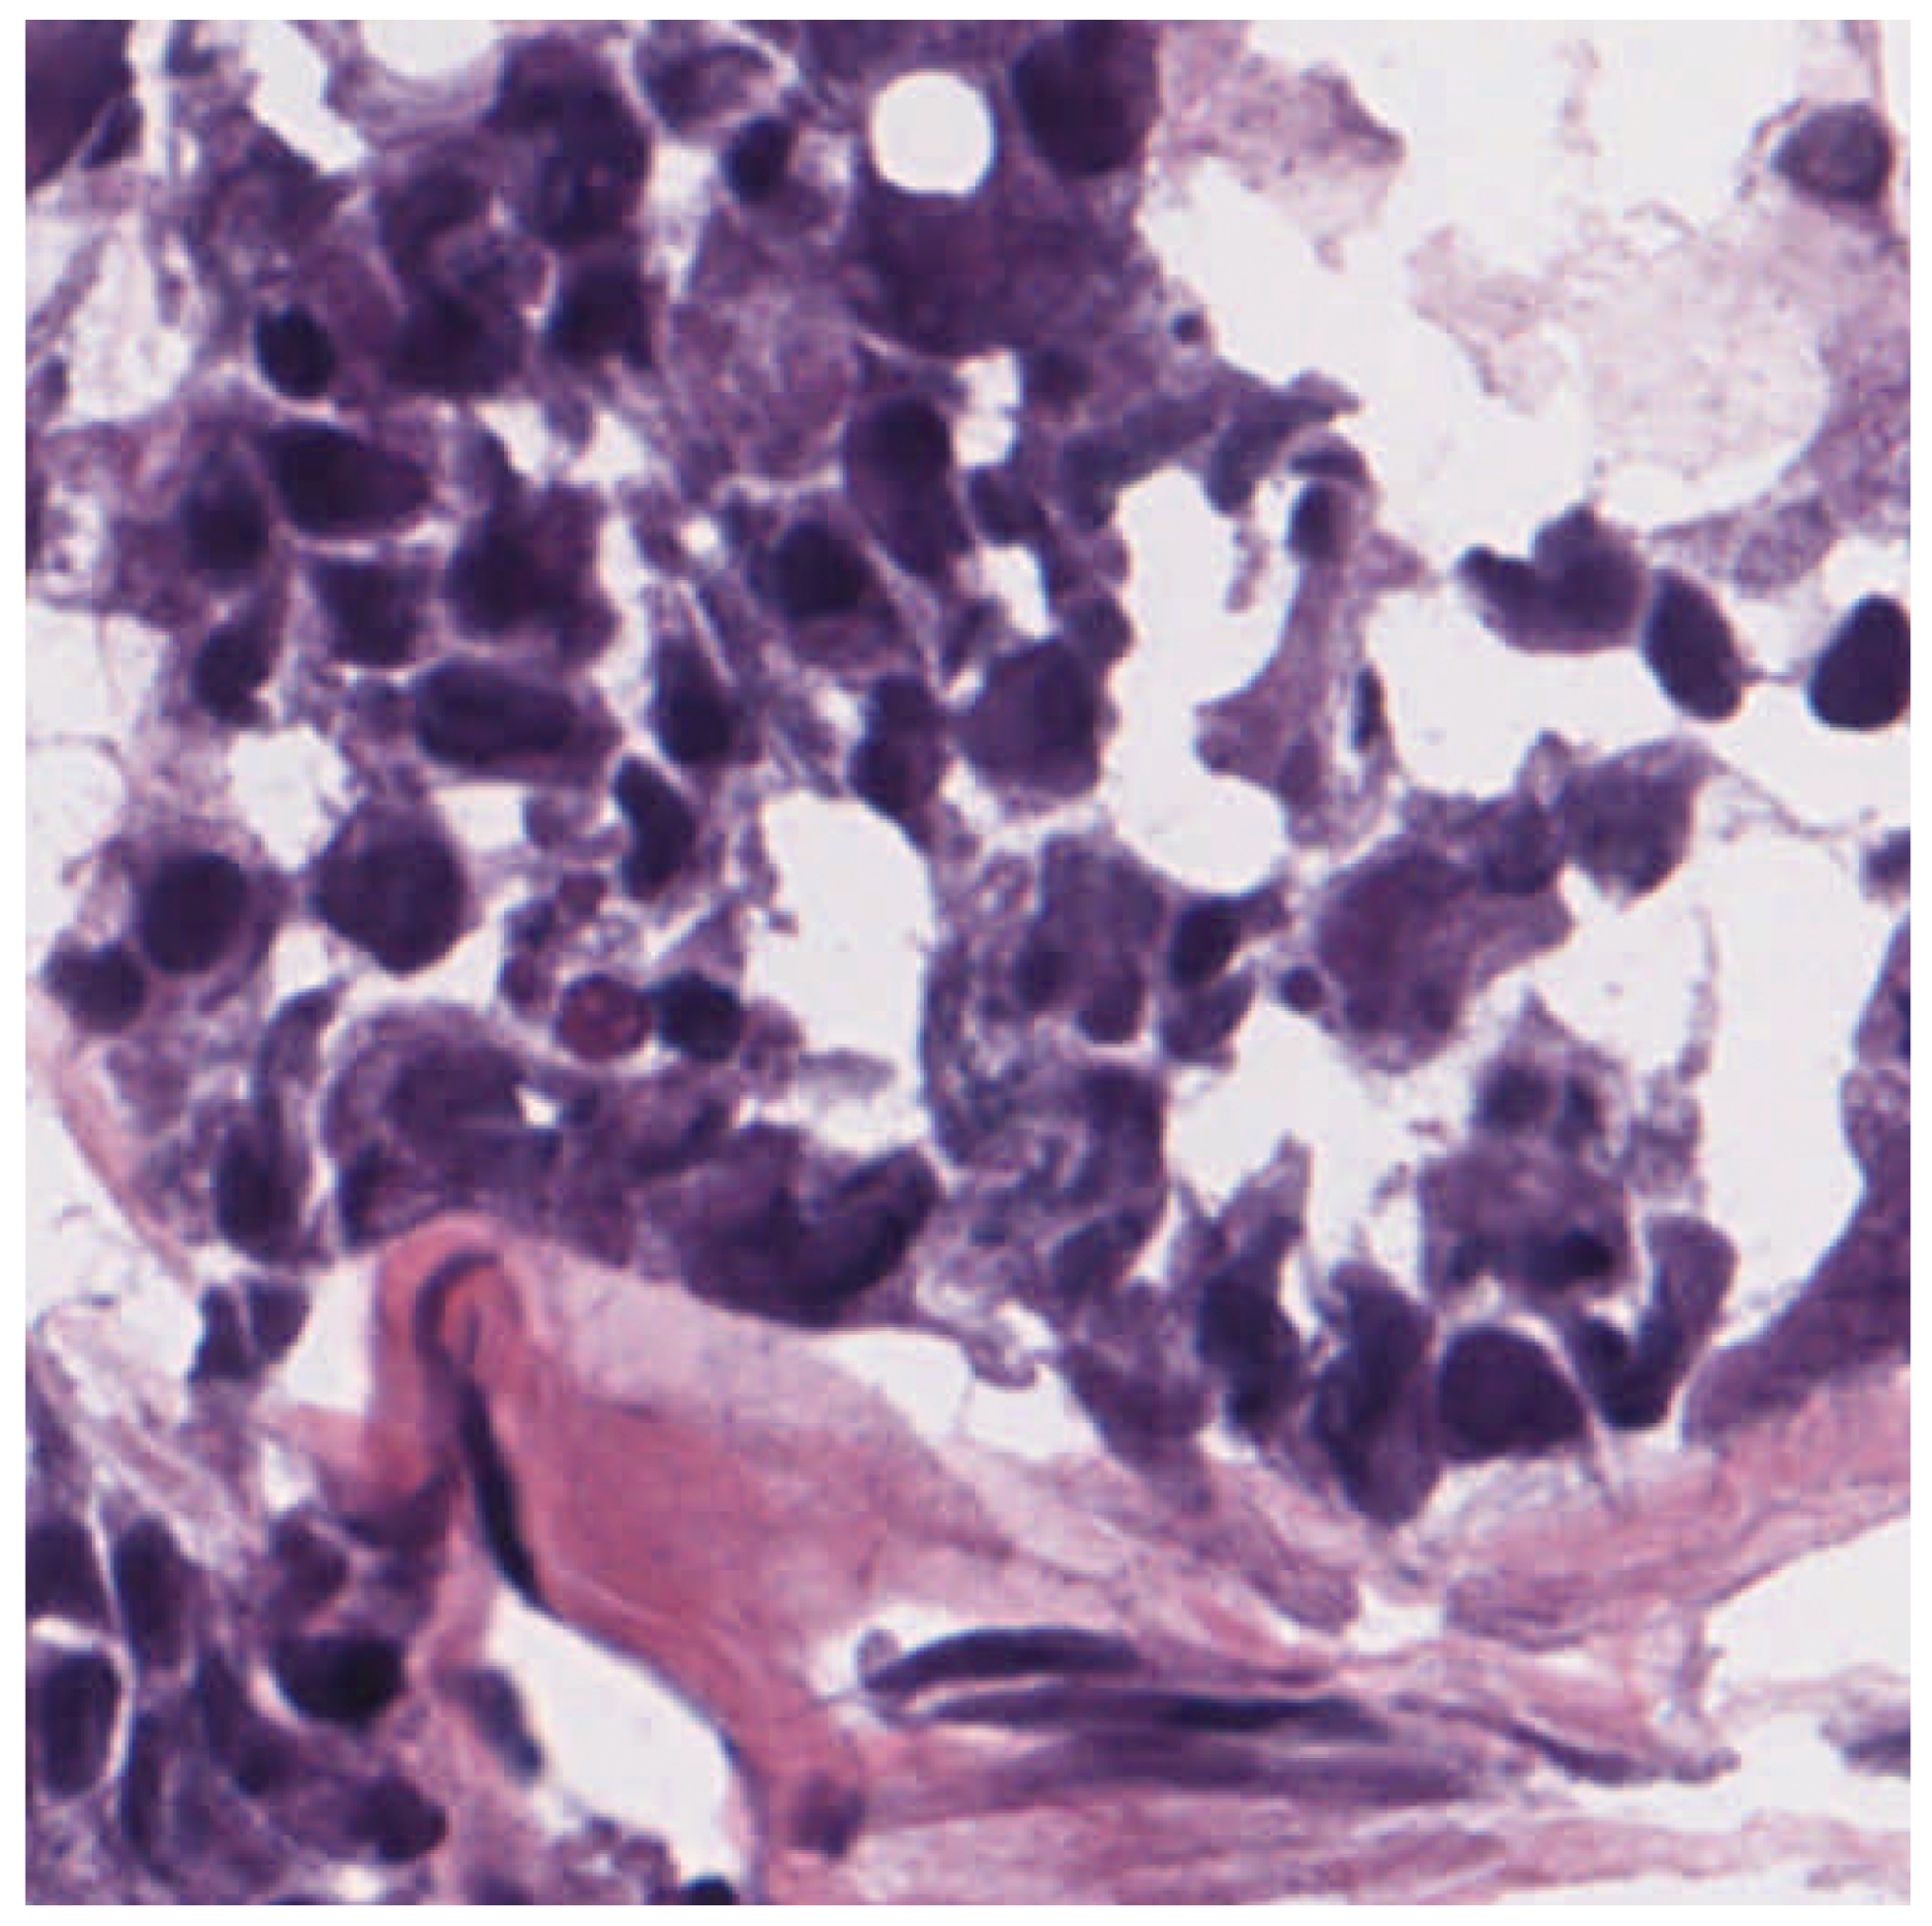

3.3. Dermatopathology

- Olsen, T.G.; Jackson, B.H.; Feeser, T.A.; Kent, M.N.; Moad, J.C.; Krishnamurthy, S.; Lunsford, D.D.; Soans, R.E. Diagnostic Performance of Deep Learning Algorithms Applied to Three Common Diagnoses in Dermatopathology. J. Pathol. Inform. 2018, 9, 32. [Google Scholar] [CrossRef]

- Zhang, J.; Zhang, X.; Qu, D.; Xue, Y.; Bi, X.; Chen, Z. A Deep Learning Approach for Basal Cell Carcinomas and Bowen’s Disease Recognition in Dermatopathology Image. J. Biomater. Tissue Eng. 2022, 12, 879–887. [Google Scholar] [CrossRef]